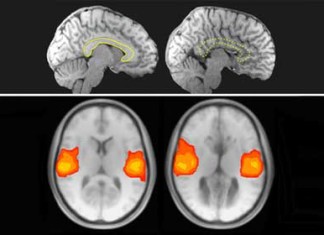

Neurocientíficos investigan comunicación del cerebro

Como un puente que cruza un río para conectar dos grandes metrópolis, el cuerpo calloso es el principal canal para el flujo de información entre los hemisferios derecho e izquierdo de nuestro cerebro. Ahora,...